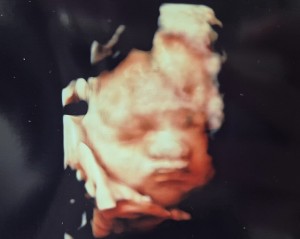

안녕하세요 귀여운 우리 딸보구 가세용

닉네임_이*솔_89

2025-08-07

42

7